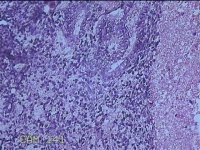

子宫腔内容物

性别

女

年龄

33岁

临床诊断

子宫内膜息肉?子宫异常出血

一般病史

阴道流血12天。

标本名称

大体所见

;纱布一块,内有灰白暗红色不规则碎组织3.5x2.8x1.3cm一堆。

图4